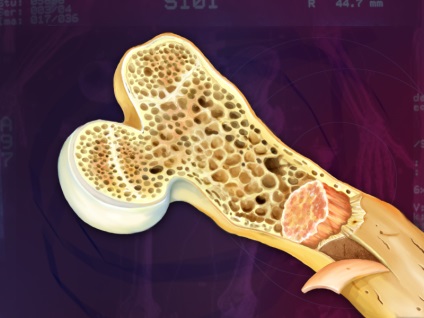

Kóros elváltozások képezik a központi része a csöves csontok a kezek és lábak, lapocka, gerinc, koponyacsontok és a nyirokcsomók és a lép. Ha több zsebek a rák folyamat akkor diagnosztizálják, myeloma multiplex. Ha a tumor lokalizálódik egy helyen - a magányos.

A jellemző áramlási mielomatoza feloldja a csont szakaszok helyén a patológiás sejt lokalizáció. A folyamat az élet megváltozott plazmasejtek citokineket, amelyek aktiválják az osteoclastok - különleges sejtek, amelyek részt vesznek a folyamatban csontforgalom. Amikor az egyensúly az osteoblast és osteoclast aktivitást mellett az első oldódási sebessége az ásványi komponens a csont-kollagén és megsemmisítése sokszor a képződési sebességét új szövet. Ezáltal zsebek felszívódást (megszüntetés), az érintett csontok törékennyé válnak és törékeny.

Kalcium az oldott szervetlen mátrixot a csontszövet bemegy a vérben, és létrehoz egy extra terhet a vesére, alkotó saját alépítményeikhez, kemény kövek. Azonban, jelenlétében mielóma betegség érinti nemcsak a vese, a csont és a nyirokrendszer. Parafehérjék, állt ki a véráramba, letétbe zsigeri (belső) szervek és ízületek formájában fehérje-poliszacharid vegyület - amiloid, ami végül kezdődik, hogy megzavarják sejtek működését.

- törékeny csontok a helyszínen tumorsejt lokalizáció;

- csontfájdalom;

- mellkasi deformáció miatt a oldódása a csigolyák és / vagy lerövidítése a többi érintett csont helyeken;